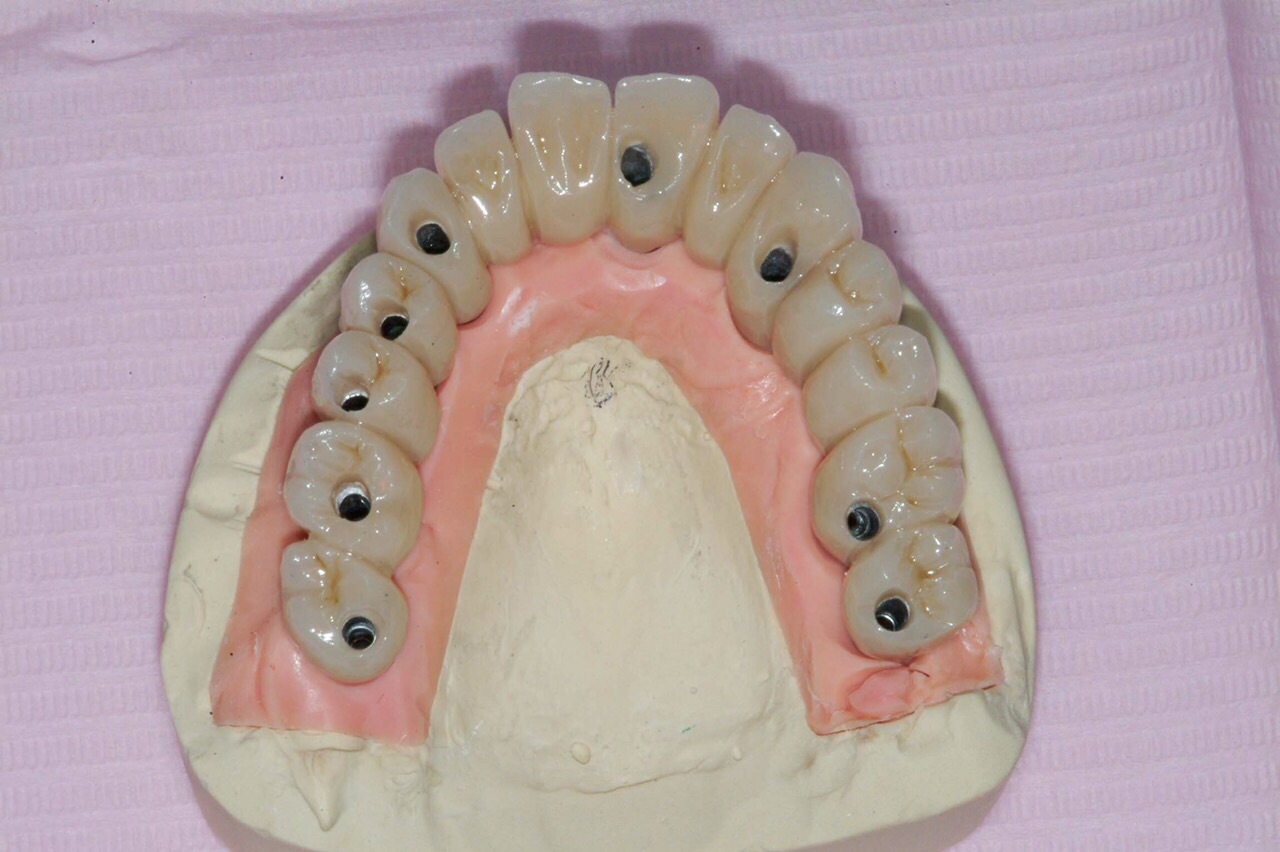

Dott.ssa ERIKA BARBALONGA PIEZOSURGERY in oralchirurgie und direkten IMPLANTOLOGIE Mit der Anwendungstechnik Piezosurgery fuehrt man Eingriffe in Oralchirurgie alls (Aufbau der Kiefernhole, Innenknochen Zystektomie, Wurzelspitzenresktion, komplizierte Extraktionen, Implantatrvorbereitung...) um Traumas zu verhindern und mit Genmanipulazion des Knochens fuer eine rapide Heilung. Ausserdem ist die Verwendung sehr innovativ und effizient fur die Implantatechnik und Knocheregeneration, die uns erlauben Rehabilitazion fur Prothetikpazienten und Steigerung der Stabilitaet der mobilen Prothetik. Mit der direkten Belastung, fixe Zaehne innerhalb in 24 h! Mit geringer invasiven Behandlung und ohne Stress, dank der chirurgischen Piezosurgery - Technik und der Sedierung (Beruhigungsmittel/Narkose) Führen Oralchirurgie mit minimal-invasiven Techniken : - Komplexe Zahnextraktionen ( verlagerte Zähne , überzählige Zähne dysodontiasis ) - Entfernung von Zysten , - Endodontische Chirurgie ( Wurzelspitzenresektion ) - Parodontalchirurgie (Zahnfleisch-Aufklappung , Knoch- und Schleimhauttransplantate ) . - Sinuslift FRUEHERKENNUNG VON MUNDKREBS Unser Engagment in der Foerderung der Kultur der oralen Gesundheit und Praevention im allegemeinen weiterhin hochaktuell, speziell die onkologische Praevention stellt eine der Saeulen unseres Geschaefts. Die fruehzeitige Erkennung von Veraenderungen der Mundschleimhaut erhoehen erheblich die Ueberlebenschancen im Falle von Krebs der Mundhoehle. Fruherkennung bedeutet Gewebeveraenderungen zu entdecken, bevor sie mit blassen Augen sichtbar werden. Die Loesung kommt von Gewebe - Fuoreszenz, die sie tief orale Schleimhautver - aenderungen sehen kann. Mit der speziellen Technologie koennen eine vorbeugende Diagnose untersuchen Bauteilqualitaet orale Schleimhaeute und verwalten werden. BEWUSSTE SEDIERUNG Eine effektive und effiziente Behandlung basiert in der Lage auf, in einer "ruhigen" - Situazion zu behandeln, und dies gilt fuer den Erwachsenen und den kleinen Pazienten. Angst haben, die eine zahnaerztliche Behandlung unterziehen muessen, kann unnoetige Schwierigkeiten fuer den Anwender und Pazienten erstellen. Bewusste Sedierung, mit Nasalmasken oder Intravenoes durch einen Fachmann in Anaesthesiologie, stellt eine therapeutische Waffe an, auf die sie sich verlassen koennen, um diese Themen, sowie eine Reihe von anderen Hilfsmitteln zur Entsspannung des Pazienten zu beheben.

• PROTESI FISSA E MOBILE